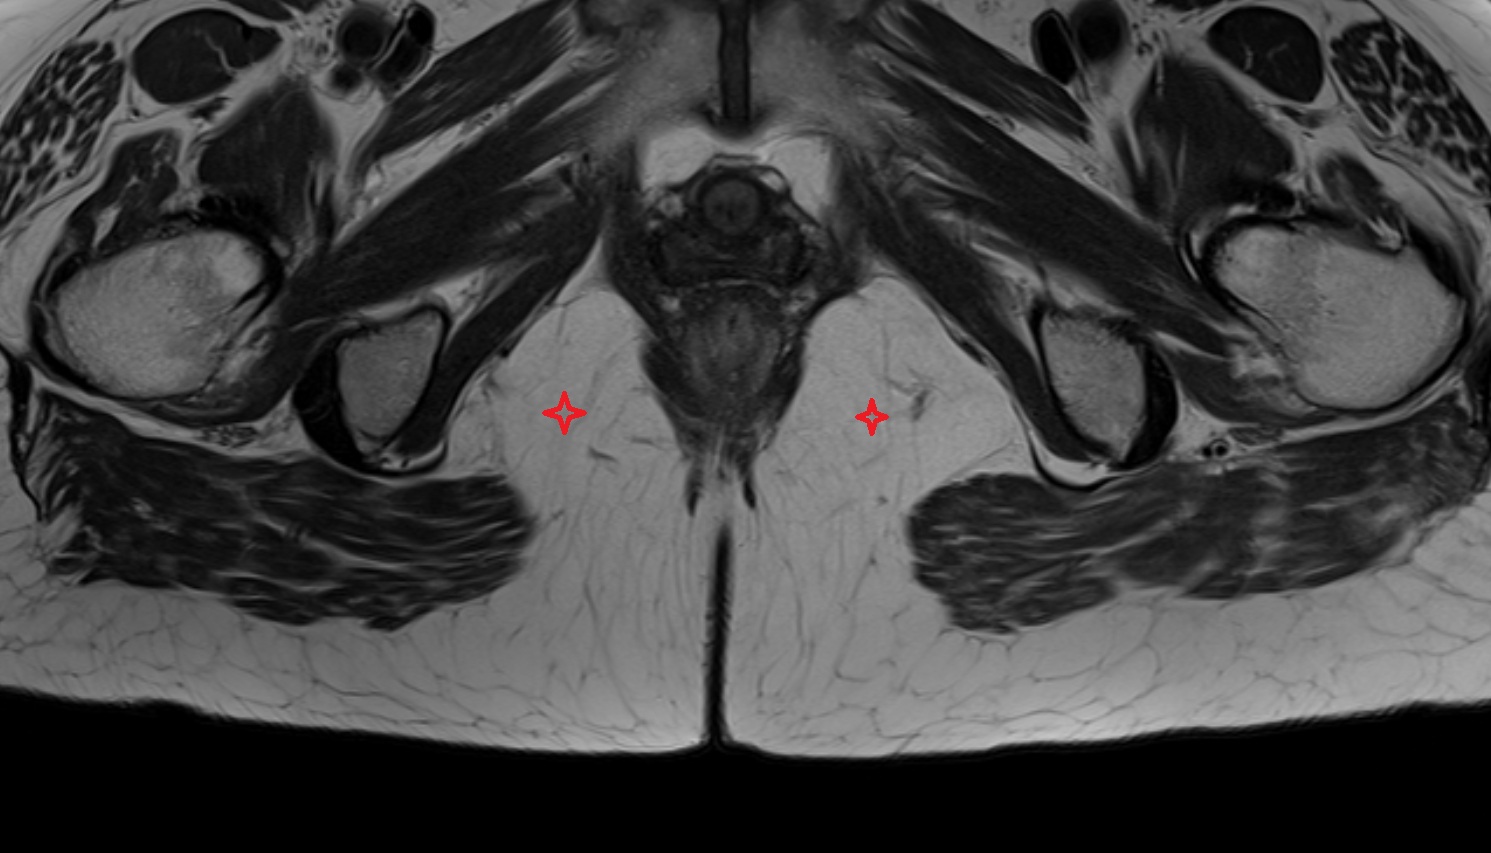

- Corpus cavernosum

- Corpus spongiosum

- Bulb of Penis

- Crus of penis